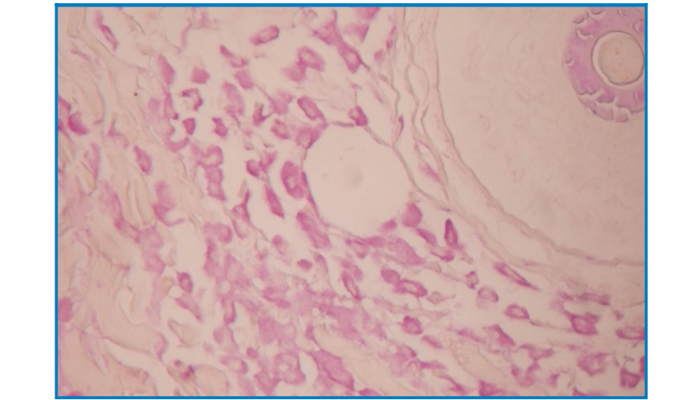

Mast Cell Stain (Aldehyde fuchsin-OG6 staining method)

Mast Cell Stain

(Aldehyde fuchsin-OG6 staining method)

Intended for staining examination of histological mast cell.